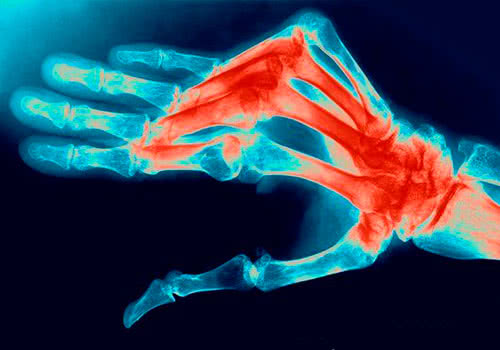

К главным симптомам ревматоидного полиартрита относятся суставные боли и деформации мелких суставов. Часто поражаются мелкие суставы кистей рук и пальцев. Для данной патологии характерна симметричность поражения суставов. В зависимости от количества вовлеченных суставов, врачи определяют стадию и вариант течения заболевания.

Деформация суставов пальцев у больного ревматоидным полиартритом

Поражение кисти - одна из главных визитных карточек полиартрита

Характерные симптомы ревматоидного полиартрита рук - прогрессирующая деформация суставов в виде "плавника моржа" или "шеи лебедя".